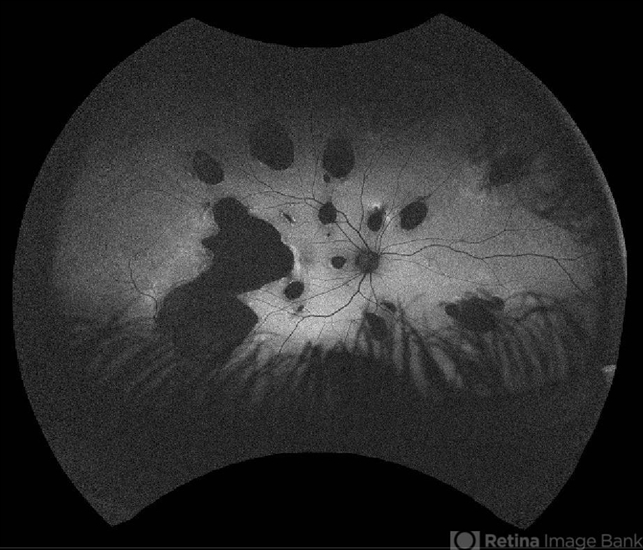

- multifocal choroiditis, multifocal chorioretinitis (MCP), inflammatory choroidopathy

- 23 -year- old man with gradually decreased vision specially in right eye, multiple lesions are in the retinal and choroidal tissue. IMCP causes episodes of inflammation that can occur bilaterally, simultaneously or separately